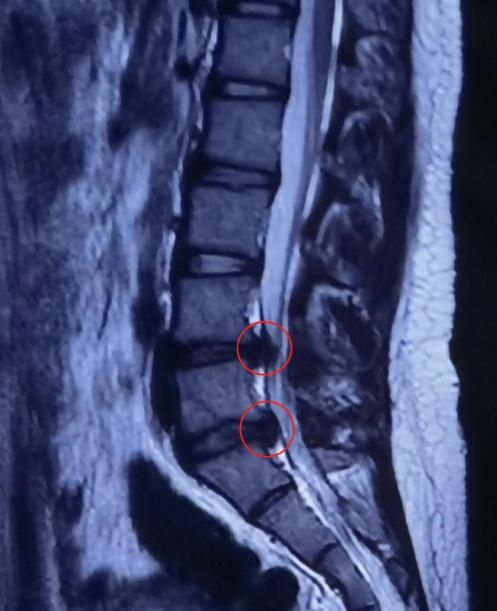

经过系统专科查体及影像学检查,发现茜茜的腰4/5、腰5/骶1椎间盘膨出,已压迫到腰5、骶1神经根。如选择保守治疗,突出的髓核在短时间内无法自吸收,且有进一步加重进而压迫到马尾神经的风险,于是,董黎强团队决定为茜茜施行“椎间孔镜下腰椎间盘突出髓核摘除”微创手术。